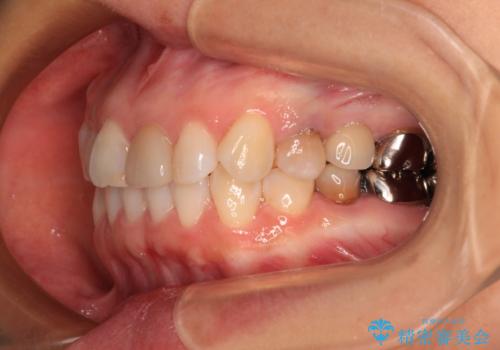

- 上下前歯のデコボコを気にして来院された患者様です。

カウンセリングにて詳しく話を聞いたところ、一番気になっているのは下顎前歯の叢生であり、上顎犬歯はあまり気になっていないとのことでした。

矯正治療は、歯の後戻りを抑制するために、治療終了後も保定装置をしっかりと使用していただくことが必須であるため、気になっている下顎だけを整えることで、その負担を半減できると考え、下顎のみの部分矯正として治療を行うこととしました。

装置としては、叢生の程度が強くなかったため、インビザラインの廉価版であるモデレート・パッケージを使用することとしました。